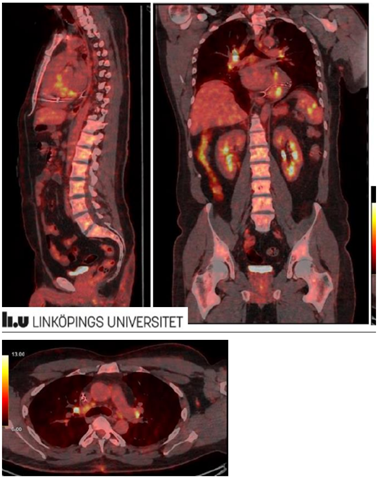

För närmare kartläggning av inflammationens utbredning utförs PET-DT

Tolka bilderna. Vilka anatomiska strukturer ”lyser” (inflammation/ämnesomsättning)?

Björn Lundberg, 38 år med yrsel, hjärtklappning och ibland svimning. Telemetri på avdelningen visar frekventa VES samt längre och korta VT med olika fokus. I samband med episoder av längre VT har Björn yrsel. Biokemiskt noteras mindre läckage av Troponin T utan dynamik. Akut ekokardiografi visar lätt nedsatt vänsterkammarfunktion samt hypo-/akinesi inferiort. MR visar kontrastuträde subepikardiellt i inferiora delar hjärtat.

Beslut fattas att lägga ICD pga. oro för framtida malign arytmi (VT/VF). Pat har inga klagomål utöver yrsel. Framkommer dock rethosta sedan drygt 6 månader

Patienten har flera gånger blivit uppmanad av hustrun att söka för hostan

Lungröntgen visar

Spirometri visar inga avvikelser

Vilka diagnoser överväger du? Vad blir nästa steg?

Vilken typ av granulomatös sjukdom är sarkoidos?

Behöver någon diagnos särskilt uteslutas innan behandlingsstart av sarkoidos med flerogansengagemang (som mjälte och hjärta)?

Vilken behandling startas?

Viktigt med skillnaden mellan icke-nekrotiserande och nekrotiserande granulomatös inflammation, då den senare pekar mot tuberkulos (vilket kräver snar handläggning av infektionsläkare).

Behandling - kortison. Det organengagemang som bedöms som allvarligast, i detta fall förstås hjärtat (där inflammationen kan vara akut livshotande utan en ICD), kommer att styra behandling och nedtrappning av kortison. Hjärtsarkoidos blir allvarlig för den drabbade patienten främst av två anledningar, den ena är risken för livshotande arytmier, den andra är risken för kronisk hjärtsvikt pga. Strukturella förändringar av myokardiet (om inflammationen lämnas obehandlad eller blir suboptimalt behandlad).